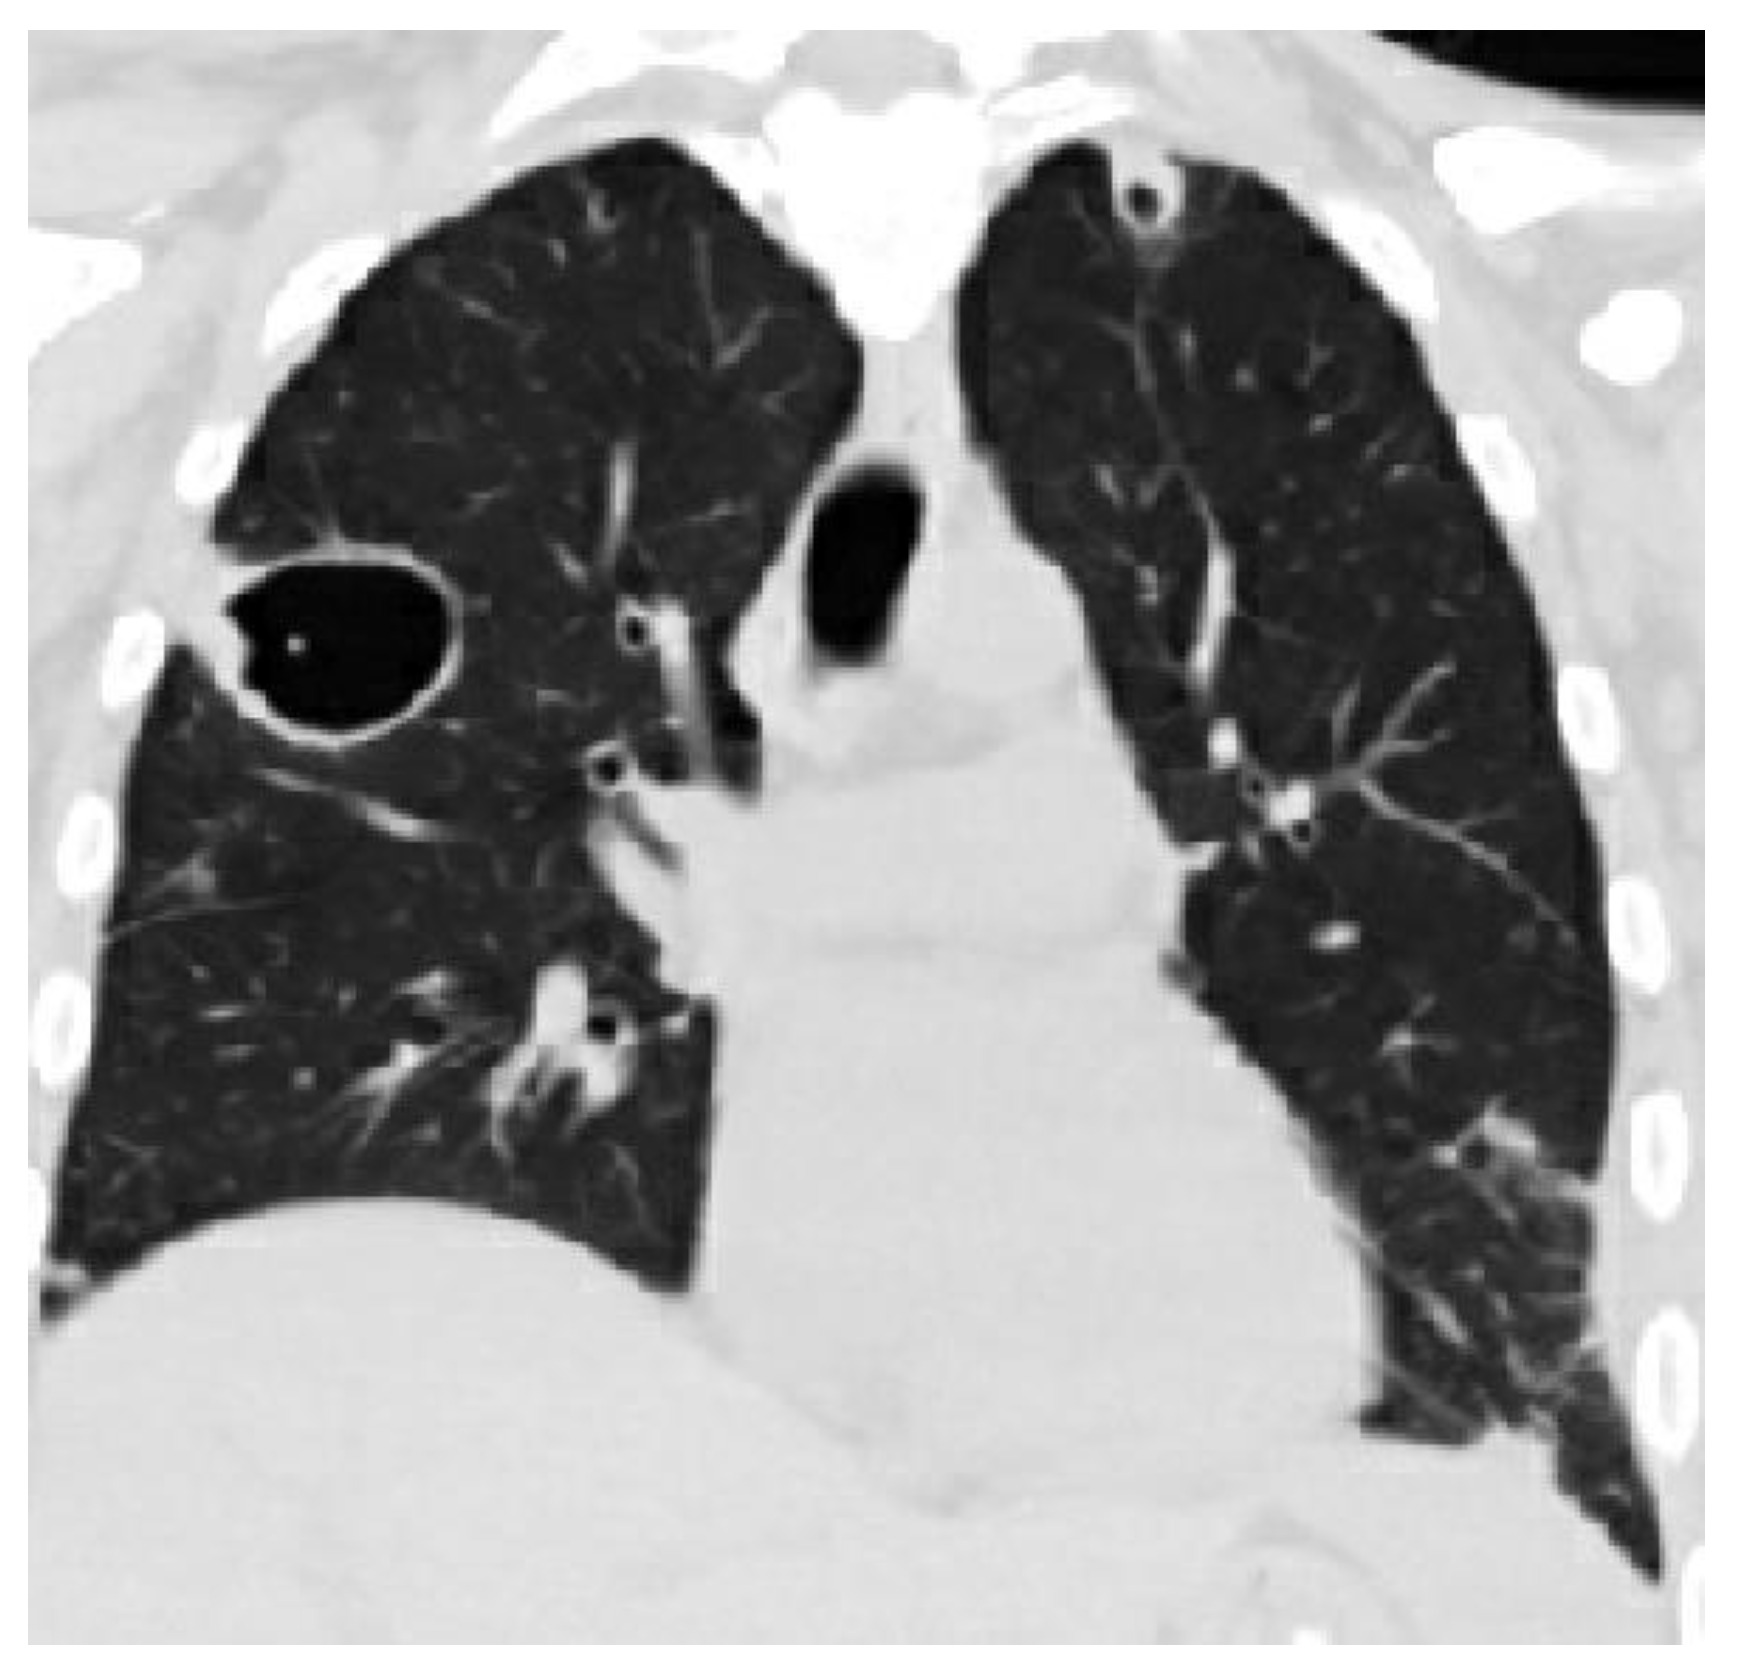

8. Radiology